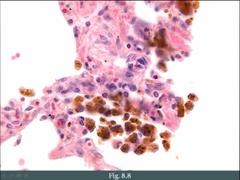

What is atherosclerosis?

Front

a disease of the arteries characterized by the deposition of plaques of fatty material on their inner walls. smooth muscle cells and macrophages within tunic intima are filled with lipid vacuoles (foam cells)

Back